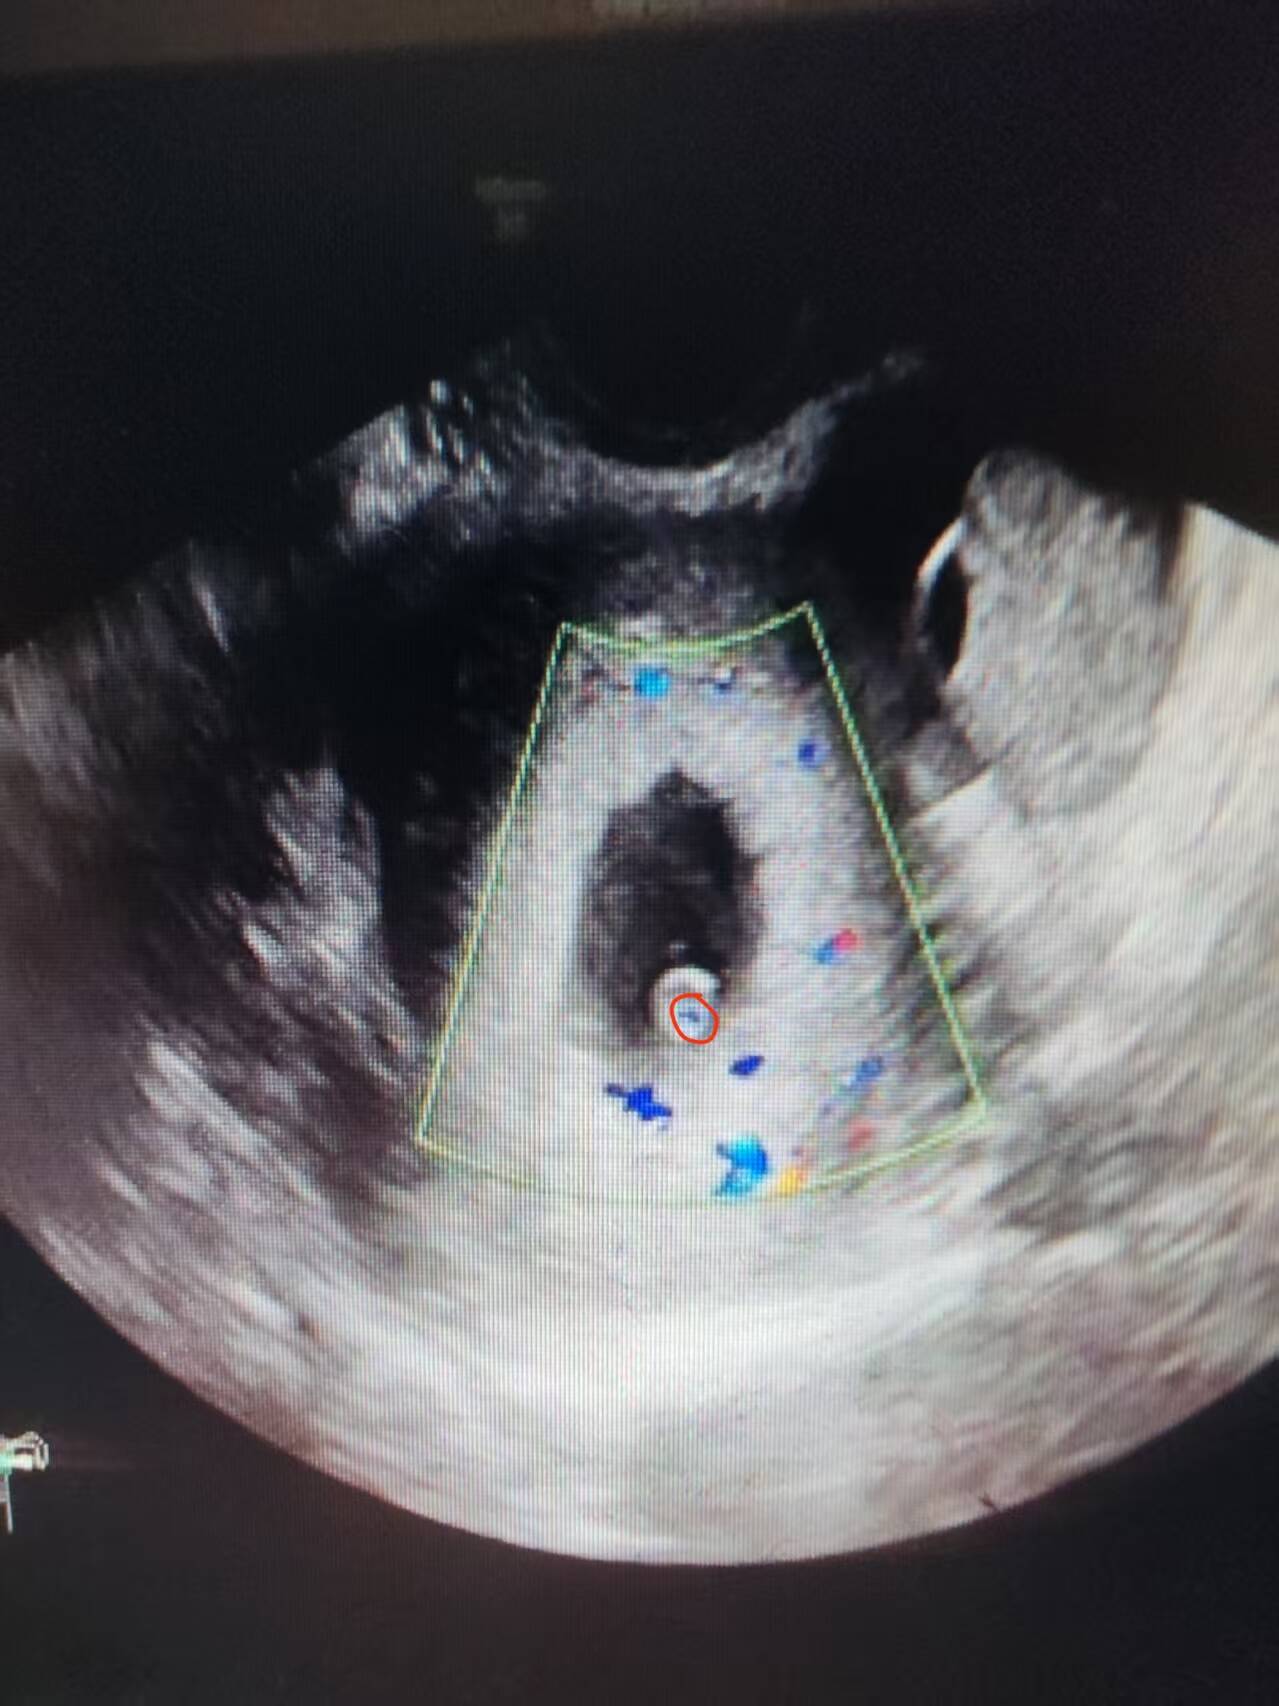

7.9 第一次B超

第一次B超

6edac89dbd20a3b7c0815e060599851a_720.pngdb30b1a6e717fd84b00b49bebe70f122_0.png第一次B超